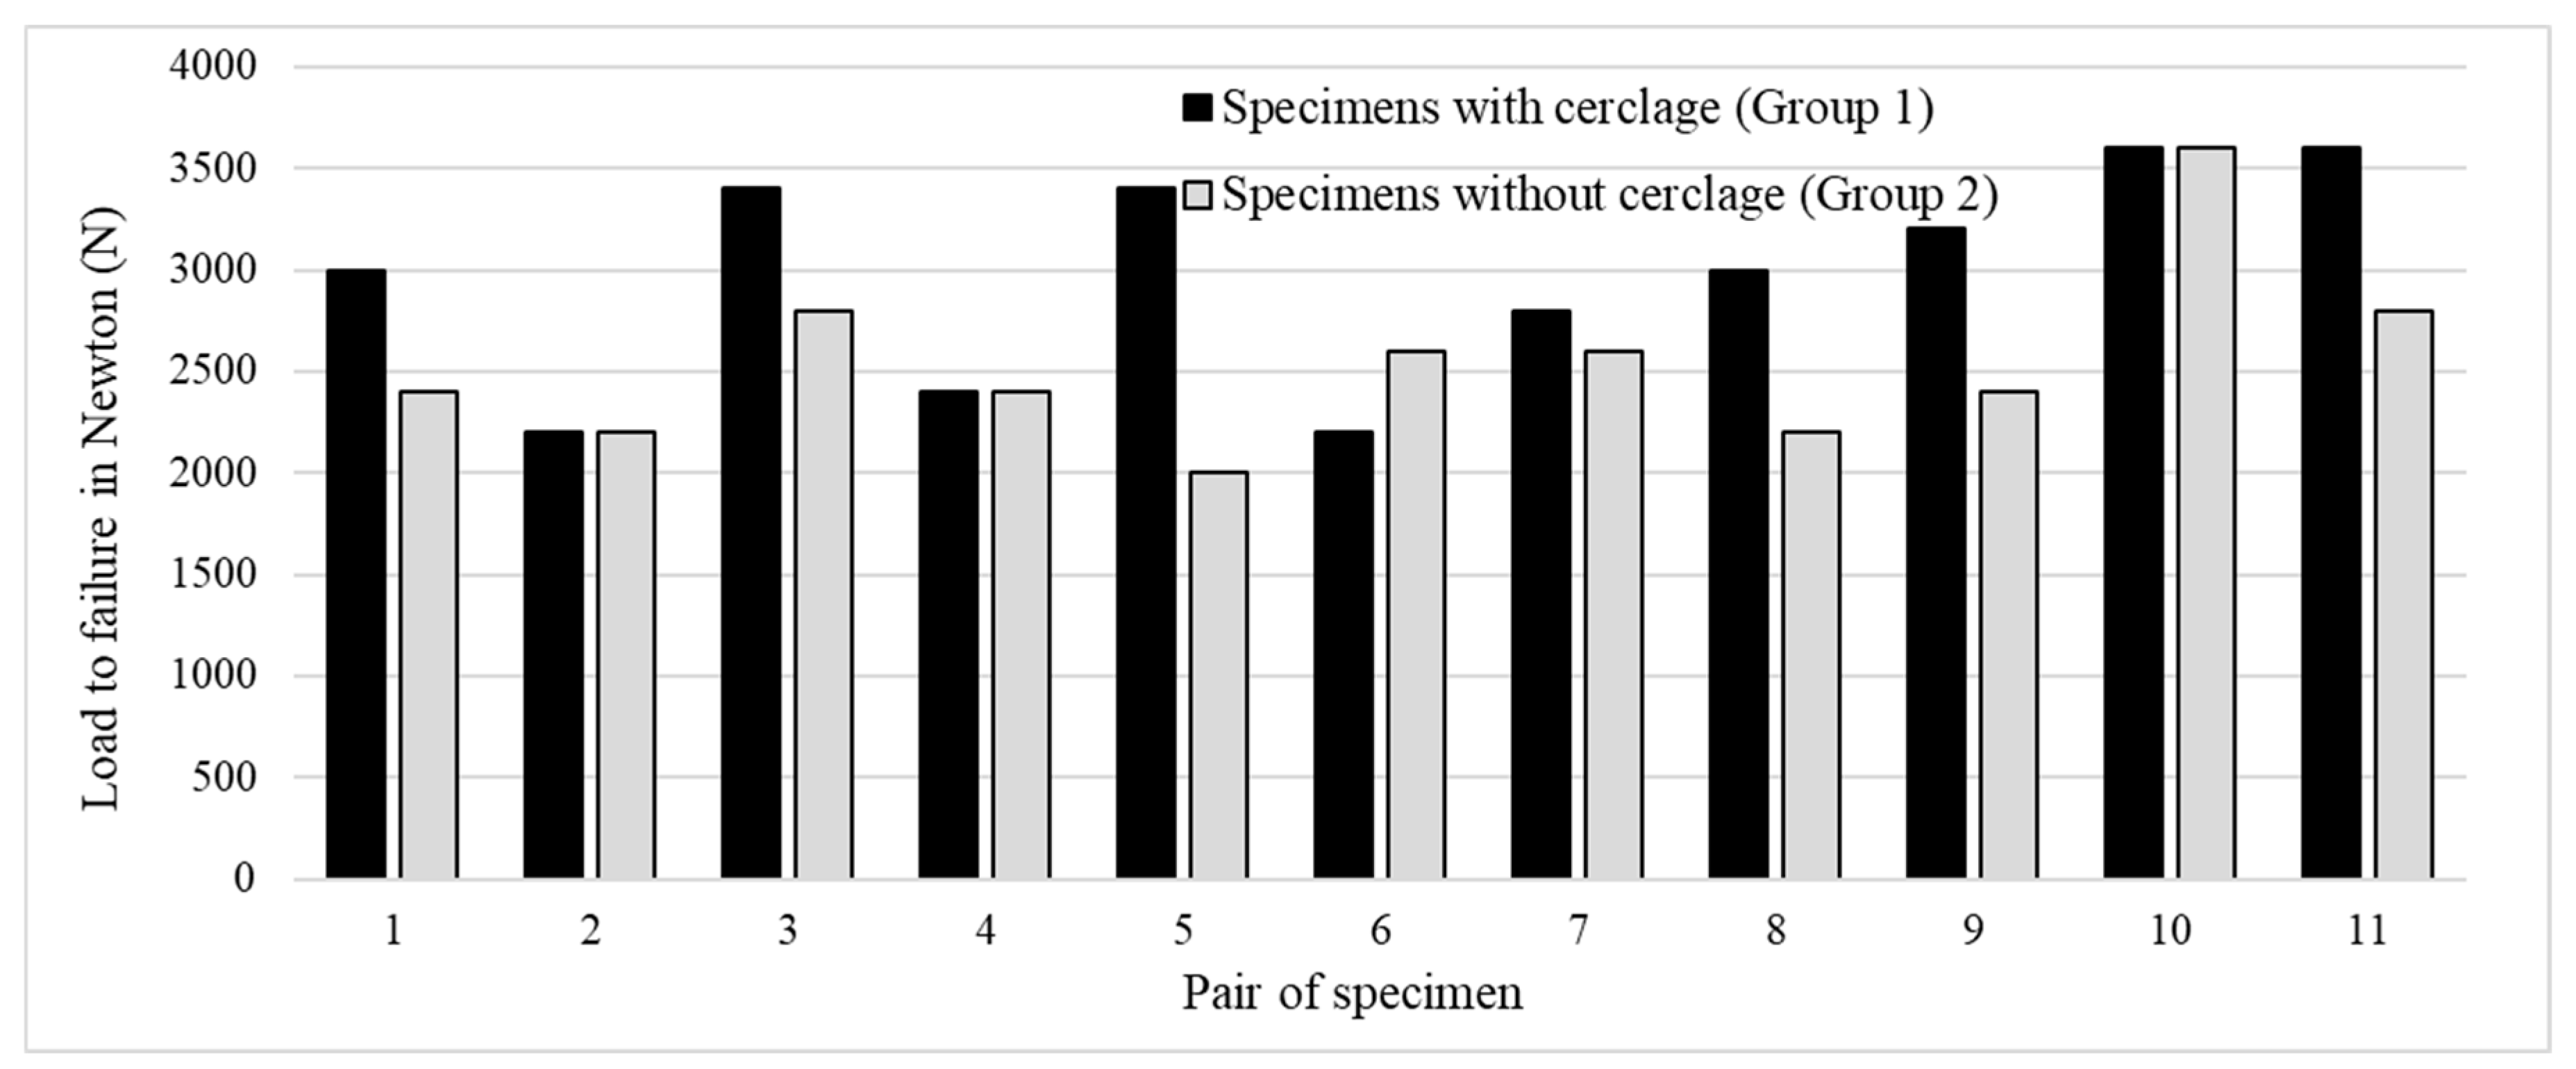

3. Results

3.2. Cyclic Testing